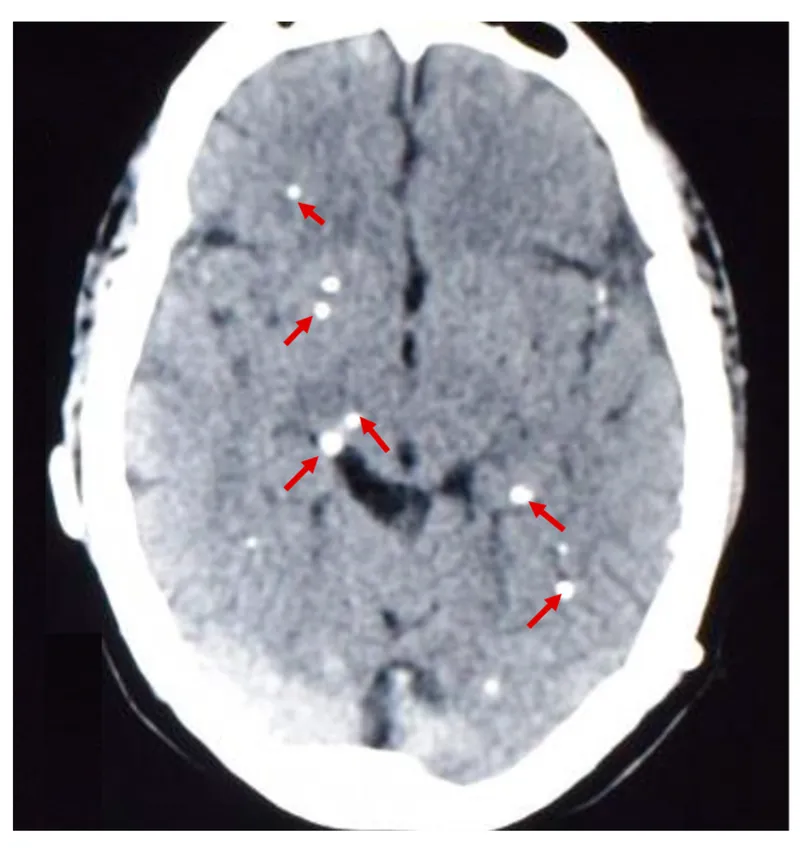

Neurocysticercosis (NCC):

- Etiology: Taenia solium larvae.

- Stages: Vesicular → colloidal → granular → calcified.

- Imaging: CT/MRI (cysts, edema, calcification).

- Rx: Albendazole; Steroids for inflammation.

⭐ Neurocysticercosis: most common parasitic CNS infection globally.

- Neurocysticercosis (NCC): Most common parasitic CNS infection; causes seizures; shows ring-enhancing lesions or calcified granulomas.